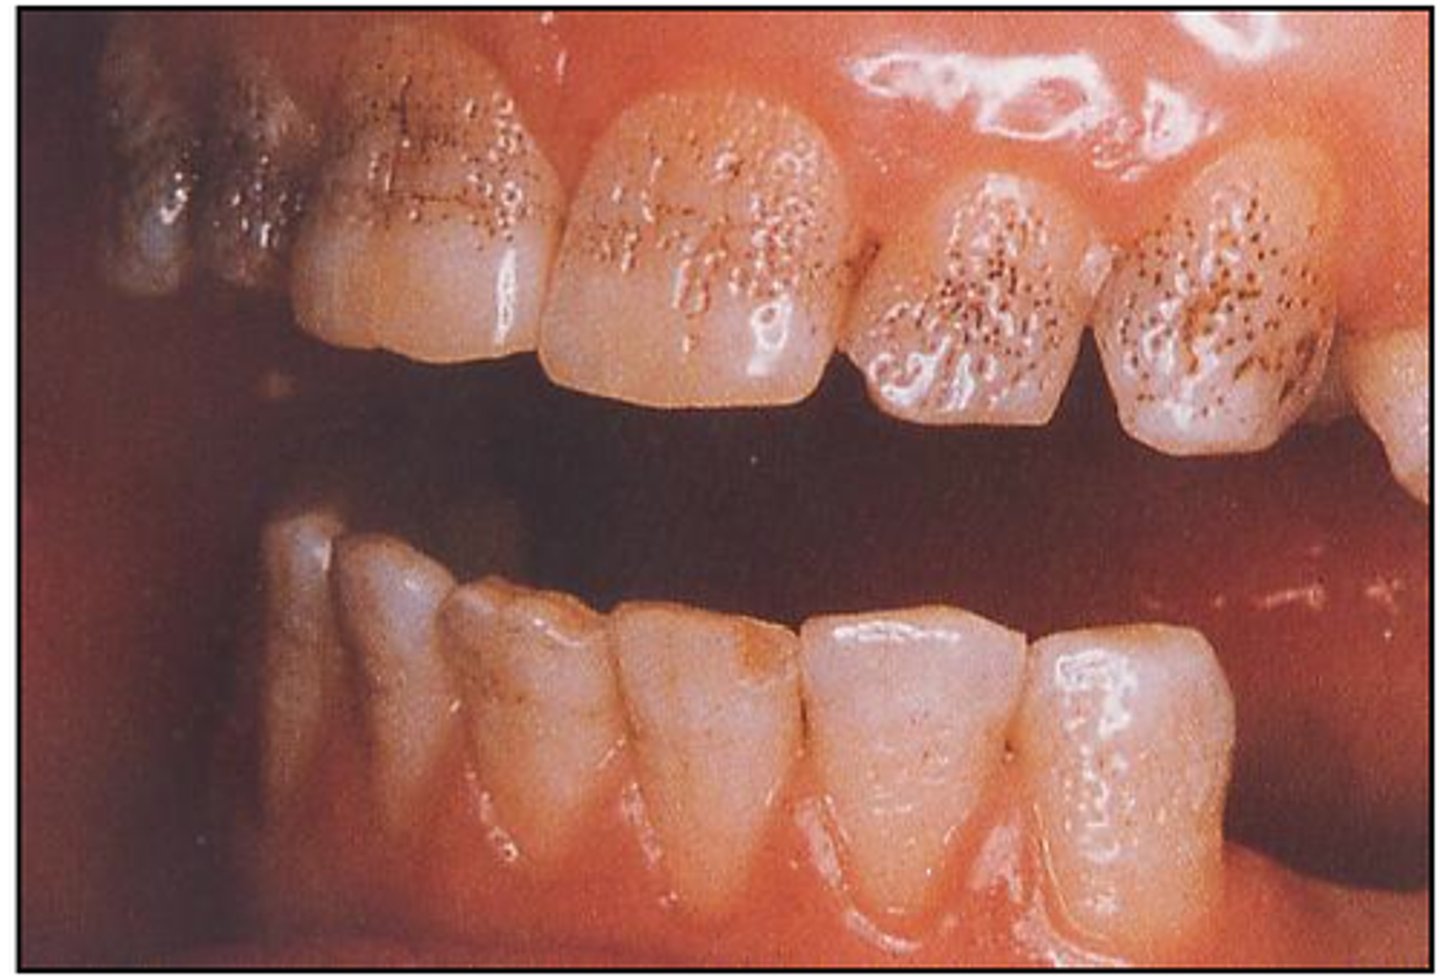

What is Amelogenesis Imperfecta?

Enamel hypoplasia

What type of enamel condition has a picket fence appearance?

Hypoplastic type